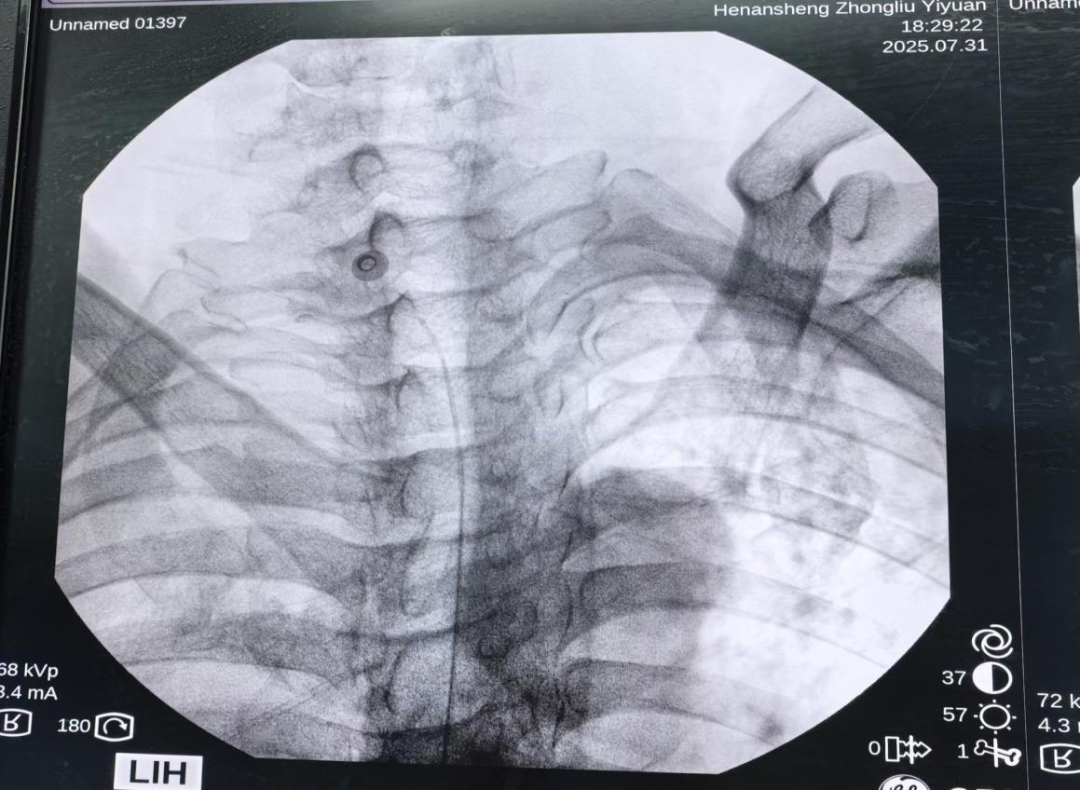

- 机器人辅助半月节电刺激治疗顽固性三叉神经痛1例 三叉神经痛是一种临床常见的面部神经痛,其特征是三叉神经分布的面部区域自发或诱发的电击样痛或刺痛,疼痛较剧烈。2018年头痛疾病国际分类第三版(ICHD-3)将三叉神经痛(TN)分为经典性三叉神经痛、继发性三叉神经痛和特发性三叉神经痛。……